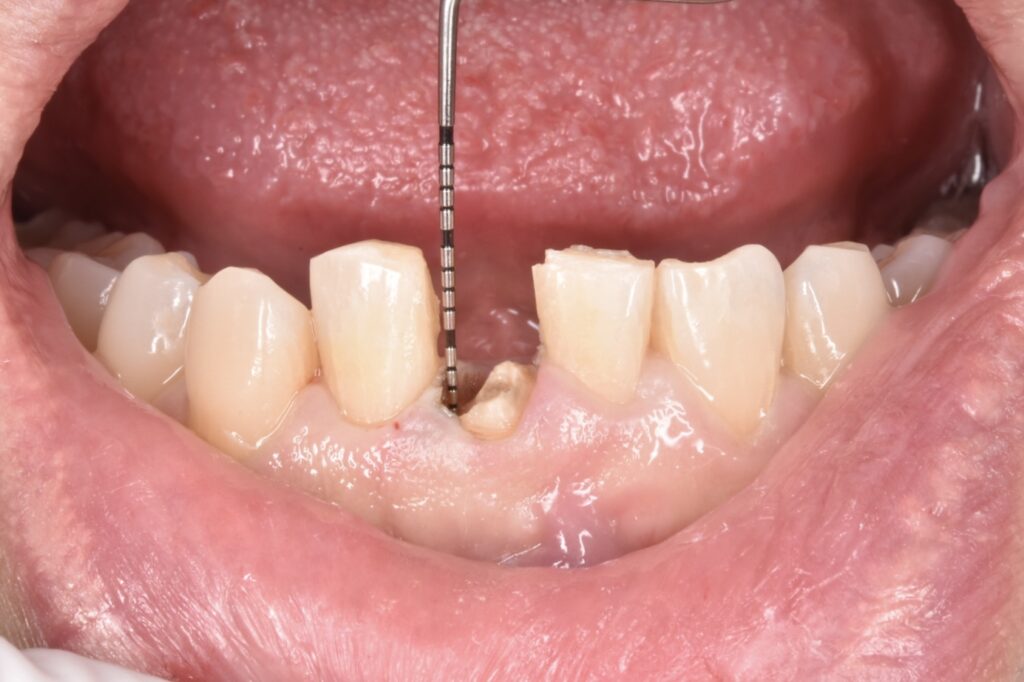

折れてしまった前歯

右下の前歯が差し歯でした。根本から折れていて一部が歯ぐきの中3ミリ近くに達しています。この破折縁から骨までは1ミリもなくこのままセラミックを被せても予後が悪いと説明させて頂きました。

歯根は無事でしたので歯根を上に引っ張り上げて使えるようにします。